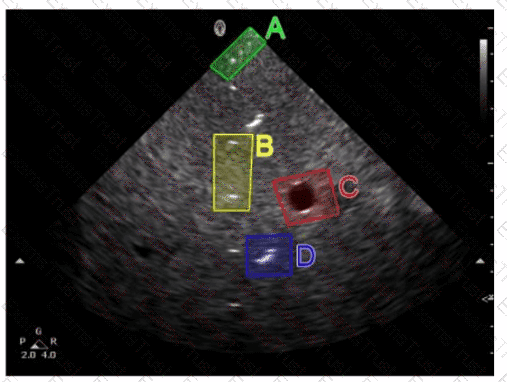

Question 26

Which resolution can be evaluated in the area indicated by the red oval in this image of a tissue-equivalent phantom?

Options:

A.

Elevational

B.

Contrast

C.

Lateral

D.

Axial